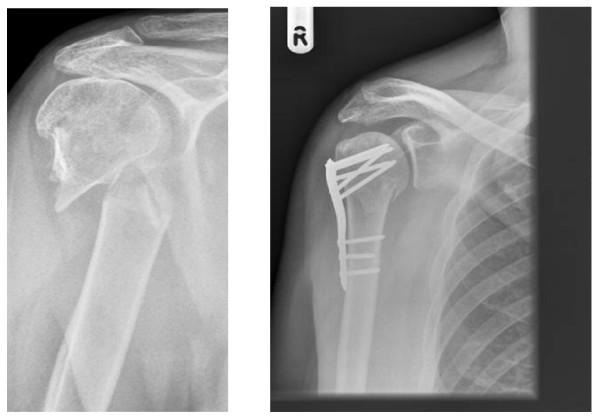

Proximal humeral fractures, which occur mainly in older adults, account for approximately 4 to 5% of all fractures. Approximately 40% of these fractures are displaced fractures involving the surgical neck. Management of this group of fractures is often challenging and the outcome is frequently unsatisfactory. In particular it is not clear whether surgery gives better outcomes than non-surgical management. Currently there is much variation in the use of surgery and a lack of good quality evidence to inform this decision.

肱骨近端骨折主要发生于老年人,约占所有骨折的 4%至 5%。其中约 40%为涉及外科颈的移位骨折。这类骨折的治疗往往具有挑战性,且治疗效果常常不尽如人意。特别是,手术治疗是否优于非手术治疗尚不清楚。目前,手术的应用存在很大差异,且缺乏高质量的证据来支持这一决策。